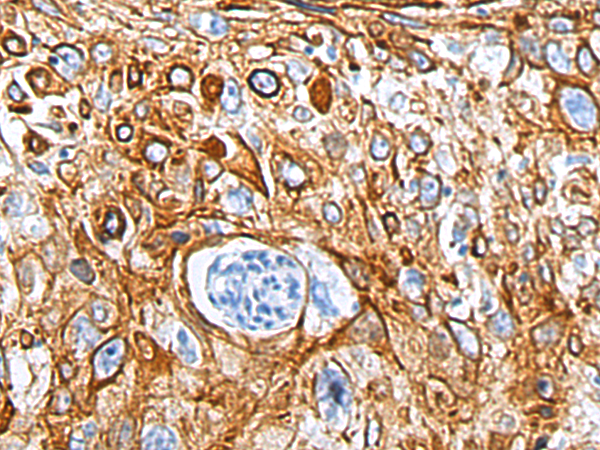

This gene encodes the type I intermediate filament chain keratin 17, expressed in nail bed, hair follicle, sebaceous glands, and other epidermal appendages. Mutations in this gene lead to Jackson-Lawler type pachyonychia congenita and steatocystoma multiplex.

WB, IHC

IHC positive control:

Human tonsil and Human cervical cancer; Human thyroid cancer and Human liver cancer

IHC Recommend dilution:

100-500